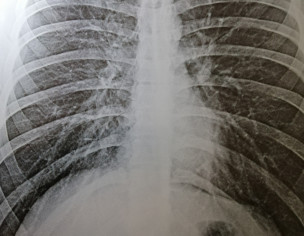

Feeling random tightness in chest from time to time with no significant difficulty in breathing. No cough or fever either. No breathing sound etc. Chest tightness gets better after taking Lexotanil. Chest XRAY is also shown. Doctors please suggest what it shows? Can it be a case of COVID? Does xray show pneumonia?

asak kindly retake proper xray

Xray findings seem to be of interstitial lung disease but confirmation may need CT but that's not important right now. It is difficult to comment without history and general physical examination.